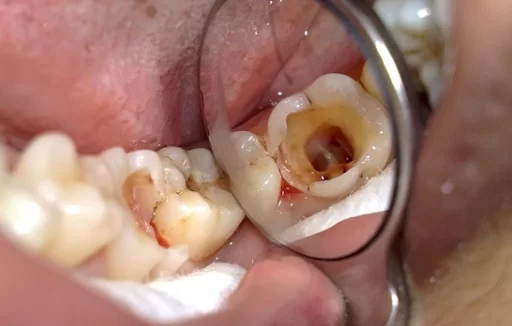

Có thể nói, sự ra đời của phương pháp bọc sứ răng hàm đã giúp nhiều người có thể lấy lại được sự tin của bản thân cũng như bảo vệ và khắc phục nhiều tình trạng răng đang gặp các vấn đề như:

- Răng bị sứt mẻ hoặc vỡ

- Răng mọc lệch khiến cho hàm răng có hình dạng không đều

- Răng thưa hoặc răng bị hô nhẹ

- Răng đang bị đổi màu, ố vàng khi dùng nhiều thuốc kháng sinh cũng như hút thuốc lá,…

Không chỉ vậy, bọc sứ còn được kết hợp với phương pháp cấy ghép implant để phục hồi răng bị mất cũng như làm trụ cho phương pháp cầu răng. Do vậy, ngay khi đang gặp phải những trường hợp trên, các bạn hãy lựa chọn phương pháp bọc sứ răng hàm để tự tạo cho mình cơ hội làm lại cuộc đời, tân trang nhan sắc hiệu quả.